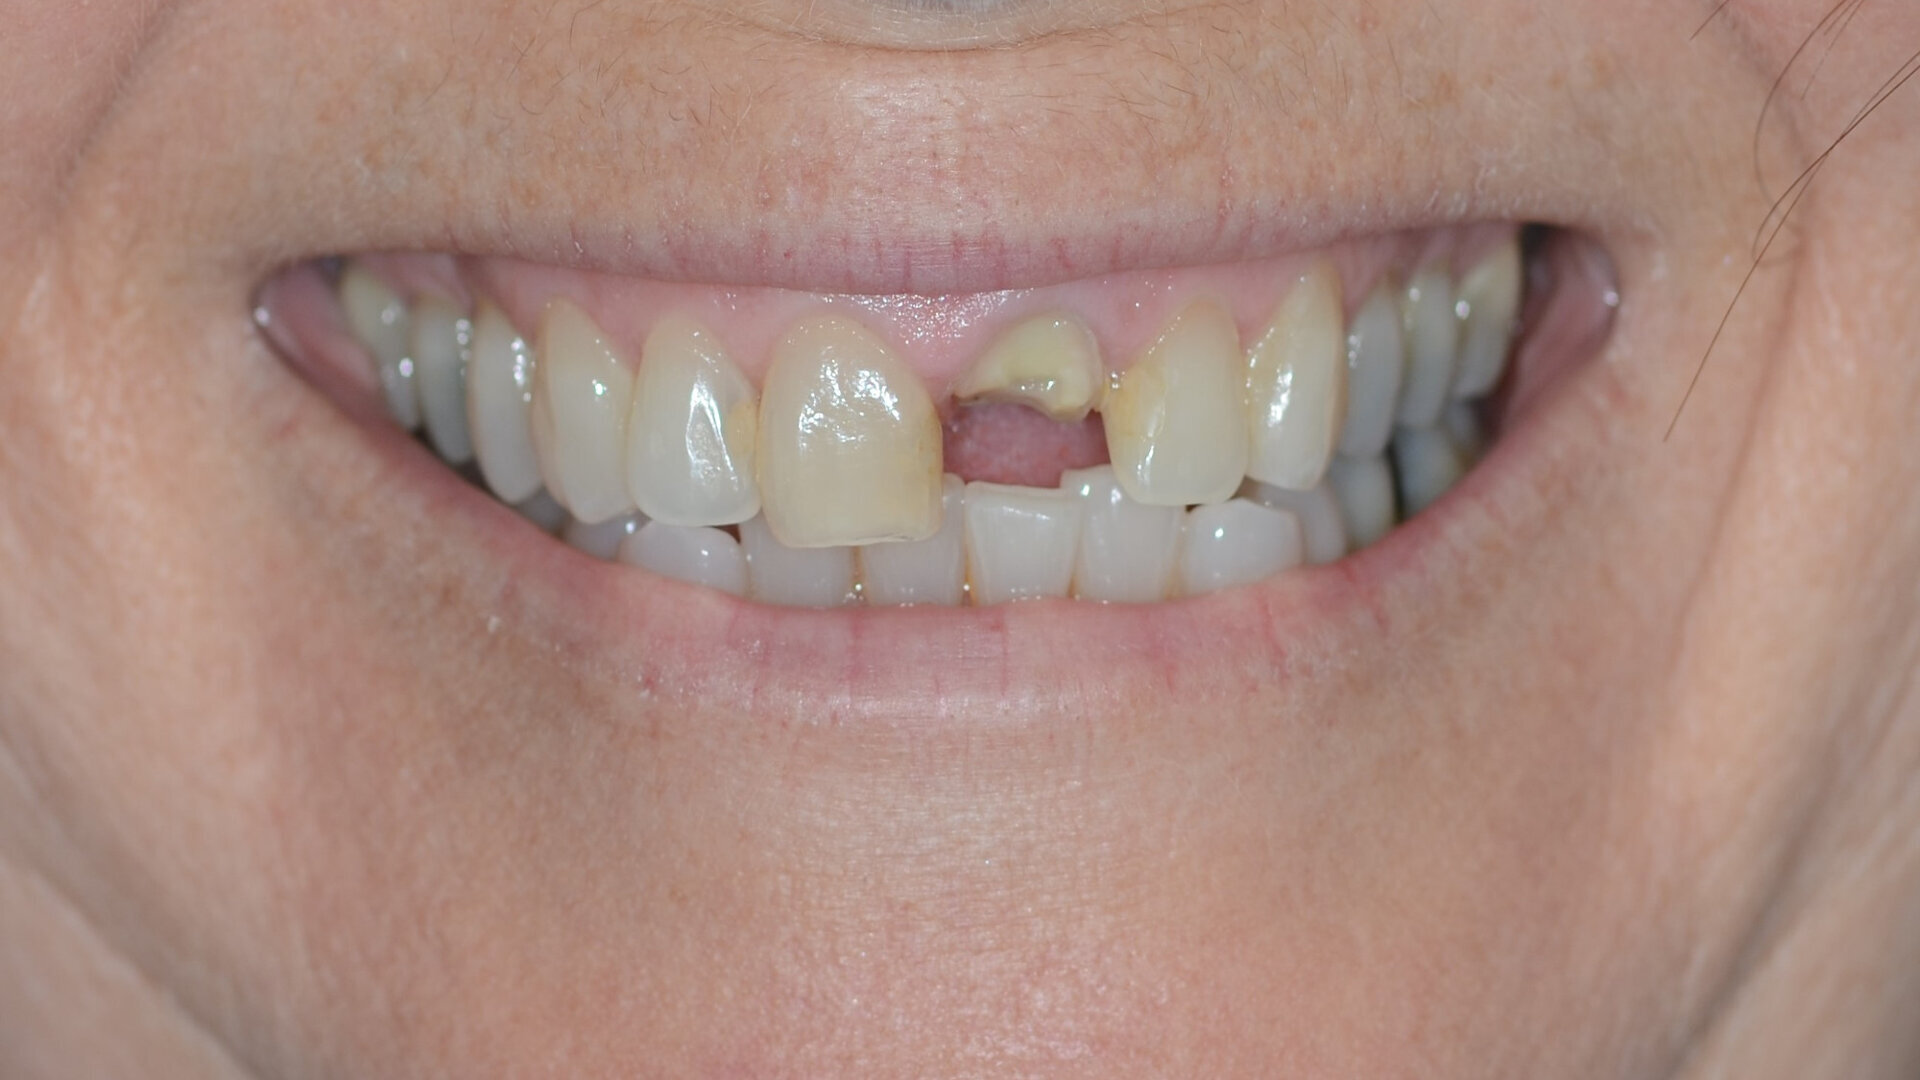

A 53-year-old female patient presented to the office with a fractured left central incisor which had been repeatedly bonded to a ceramic crown (Figs. 1 & 2). Anamneses and examination established good systemic and oral health, a well-balanced occlusion and no smoking habits. Cone beam computed tomography (CBCT) and a periapical radiograph showed external root resorption with very limited insertion into the alveolar bone, insufficient for adequate conventional intra-radicular post placement (Figs. 3 & 4). Considering that the fractured tooth was in the aesthetic zone, the patient requested restoration in the safest and fastest way possible.

Fig. 1: Initial situation, extra-oral view.

Treatment planning

Given the clinical and radiographic situation with the position of the root towards the labial wall and sufficient apical bone, extraction followed by immediate implant placement (Straumann BLX) and immediate restoration was chosen as the treatment option. An immediate temporary abutment would be placed and chairside tooth shell pick-up technique for the provisional restoration.